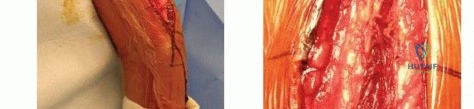

The Anterolateral Approach

The skin incision is made along a line connecting the coracoid process to the lateral epicondyle of the humerus. The length of the incision is dictated by the fracture pattern and the templated plate length. Subcutaneous tissues are dissected, taking care to identify and protect the cephalic vein, which can be retracted either medially or laterally depending on the exact proximal extent of the exposure.

The deep fascia is incised in line with the skin incision. The biceps brachii muscle is identified and mobilized medially, exposing the underlying brachialis muscle. At this juncture, the surgeon must decide on the specific handling of the brachialis muscle based on the fracture location.

For distal third fractures, the exposure must transition to the interval between the brachialis and the brachioradialis. The radial nerve emerges from the posterior compartment by piercing the lateral intermuscular septum and travels distally in the cleft between the brachialis (medially) and the brachioradialis (laterally).

To safely exploit this interval, the fascia between the brachialis and brachioradialis is carefully incised. The radial nerve must be actively identified and protected. It is often easiest to identify the nerve distally where the interval is wider and trace it proximally to where it pierces the septum. Once identified, the nerve is gently mobilized and protected with vessel loops. Retraction of the nerve must be minimal and meticulous to prevent iatrogenic neuropraxia.